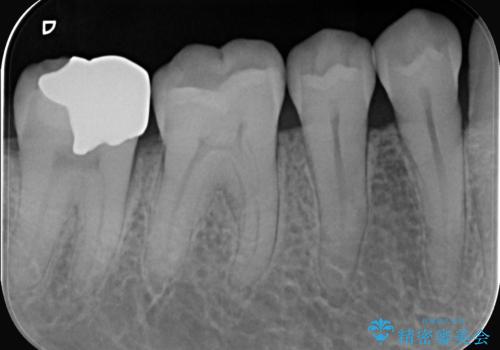

- お口の中にある銀歯を全てなくして、白く健康的な状態にしたい」という主訴でご来院されました。長年使用してきた複数の銀歯は、経年劣化により適合が悪くなっており、一部では内部で二次カリエス(虫歯の再発)も認められました。

患者様と相談の上、全ての金属(メタル)を取り除き、生体親和性が高く審美性に優れた素材へ置き換えるメタルフリー治療の計画を立案。部位や欠損の大きさに合わせ、セラミックインレーおよびセラミッククラウンを用いて、お口全体の調和を整えることとしました。

銀歯の除去と精密な再治療: 古い銀歯を一つひとつ丁寧に取り外し、内部の虫歯を徹底的に除去。神経を保護するための処置を行った上で、適合性を極限まで高めるために精密な型取りを行いました。

オールセラミックによる修復: 天然歯のような光の透過性と硬さを持つオールセラミックを使用しました。奥歯であっても、患者様固有の歯の色調や咬み合わせの溝を忠実に再現した修復物を装着。金属を一切使用しないことで、金属アレルギーのリスクを排除し、歯肉の色が黒ずむ心配もなくなりました。

【治療の結果】 全ての銀歯が白くなったことで、お口の中がパッと明るくなりました。見た目の美しさだけでなく、表面が滑らかなセラミックはプラークが付着しにくいため、将来的な虫歯や歯周病の予防効果も高まった健康的な口腔環境が実現しました。